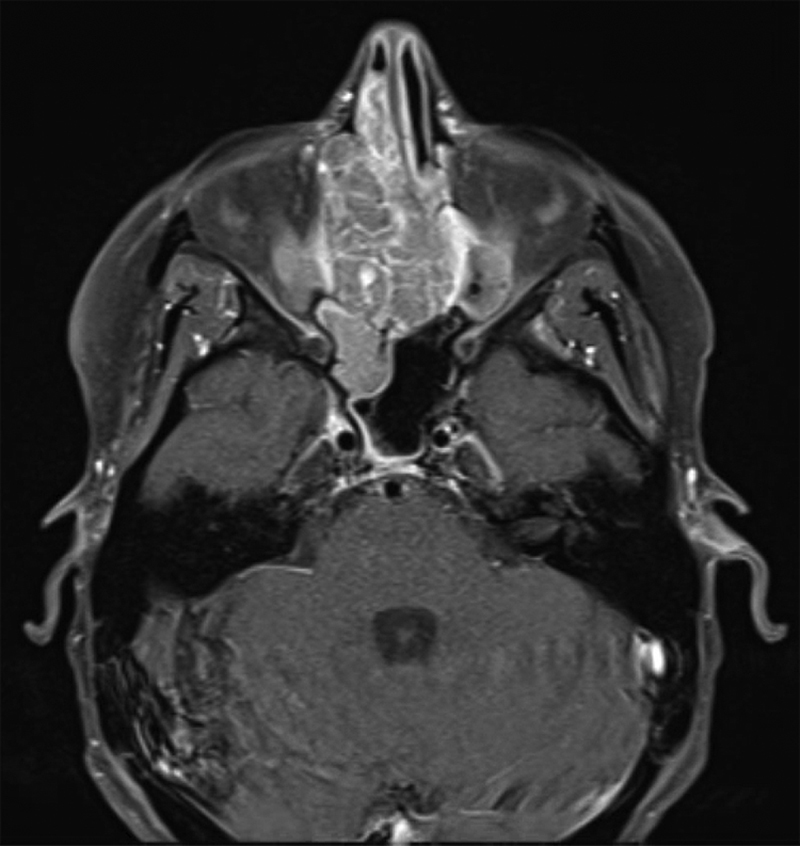

背景 放射治疗是治疗脑肿瘤的主要方法,但延迟并发症包括继发性恶性肿瘤,可能在治疗结束后数月至数年发生。方法 我们回顾了一名 41 岁女性的病历,她因复发性星形细胞瘤接受了 60 Gy 的放射治疗,6 年后又患上了局部晚期鼻窦畸胎肉瘤。我们检索了MEDLINE、Embase和Web of Science,对曾因脑肿瘤接受过头颅照射的患者中经活检证实的鼻窦恶性肿瘤进行了范围界定。结果 据我们所知,这是首例因脑瘤接受颅内照射后出现鼻窦畸胎肉瘤的患者报告。我们对 1907 项研究进行了范围审查,发现了 14 例类似的继发性鼻窦恶性肿瘤病例。原发癌诊断的中位年龄为 39.5 岁(标准差 [SD]:21.9),中位放射剂量为 54 Gy(标准差:20.3)。原发性癌症与继发性鼻窦癌之间的中位潜伏期为 9.5 年(标准差:5.8)。嗅神经母细胞瘤是最常见的鼻窦癌(4 例)。50%的患者在1.5年内死于鼻窦癌。结论 因治疗原发性脑肿瘤而接受鼻窦部位放射线照射(包括低剂量或散射辐射)的患者可能会面临日后罹患继发性鼻窦恶性肿瘤的风险。监测高危患者的医生必须对可能提示鼻窦恶性肿瘤的症状保持警惕,监测工作应包括对整个照射区域进行放射学检查,并仔细观察是否存在继发性恶性肿瘤。

Background  Radiation therapy is a mainstay of treatment for brain tumors, but delayed complications include secondary malignancy which may occur months to years after treatment completion. Methods  We reviewed the medical records of a 41-year-old female treated with 60 Gy of radiation for a recurrent astrocytoma, who 6 years later developed a locally advanced sinonasal teratocarcinosarcoma. We searched MEDLINE, Embase, and Web of Science to conduct a scoping review of biopsy-proven sinonasal malignancy in patients who previously received cranial irradiation for a brain tumor. Results  To our knowledge, this is the first report of a patient to present with a sinonasal teratocarcinosarcoma after receiving irradiation for a brain tumor. Our scoping review of 1,907 studies produced 14 similar cases of secondary sinonasal malignancy. Median age of primary cancer diagnosis was 39.5 years old (standard deviation [SD]: 21.9), and median radiation dose was 54 Gy (SD: 20.3). Median latency time between the primary cancer and secondary sinonasal cancer was 9.5 years (SD: 5.8). Olfactory neuroblastoma was the most common sinonasal cancer ( n  = 4). Fifty percent of patients died from their sinonasal cancer within 1.5 years. Conclusion  Patients who receive radiation exposure to the sinonasal region for treatment of a primary brain tumor, including low doses or scatter radiation, may be at risk of a secondary sinonasal malignancy later in life. Physicians who monitor at-risk patients must be vigilant of symptoms which may suggest sinonasal malignancy, and surveillance should include radiographic review with careful monitoring for a secondary malignancy throughout the entire irradiated field.